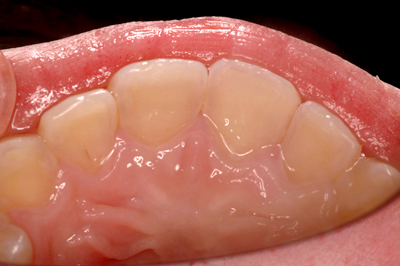

インプラント施術例

歯を削りたくない、入れ歯をどうしても入れたくないという時、インプラント治療を行っています。

施術後